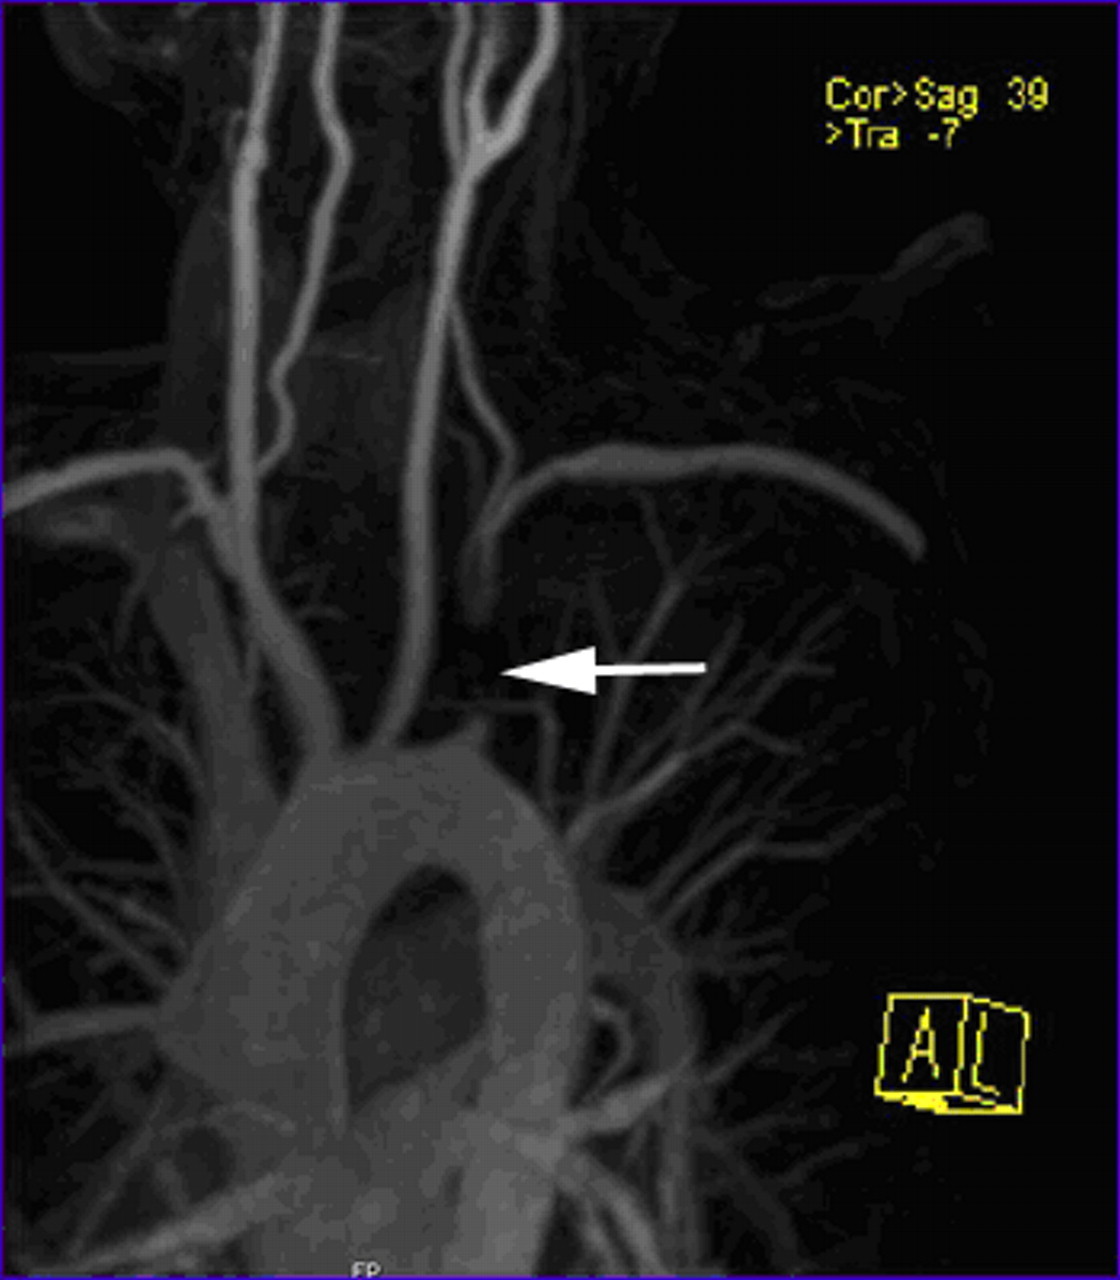

SUBCLAVIAN STEAL SYNDROME

This condition is due to stenosis of the subclavian artery resulting in “stealing” of blood to the arm by retrograde flow in the ipsilateral vertebral artery

The commonest cause is atherosclerotic disease. Other acquired causes include:

Further Management:

CT to identify:

Surgical or interventional radiology referral for: